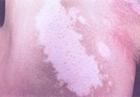

因皮膚上出現白色斑片,故名。又稱「白瘢風」。由於風邪襲表,腠理 不密,氣血失和而發。多見於青壯年,亦見於兒童及老人。可發於任何部位,症見大小不等之乳白色斑塊,與正常皮色分界明顯,周圍皮色較 深,斑內白髮變白,部份白斑中央有褐色斑疹或淡紅色丘疹,無癢痛感 ,經過緩慢,常經久不退。

白駁風又稱 白癜風,本病的突出表現就是局部皮膚變白。皮膚變白在臨床上稱為"色素減退"。有色素減退症狀的疾病很多,常見的有如下幾種:白化病